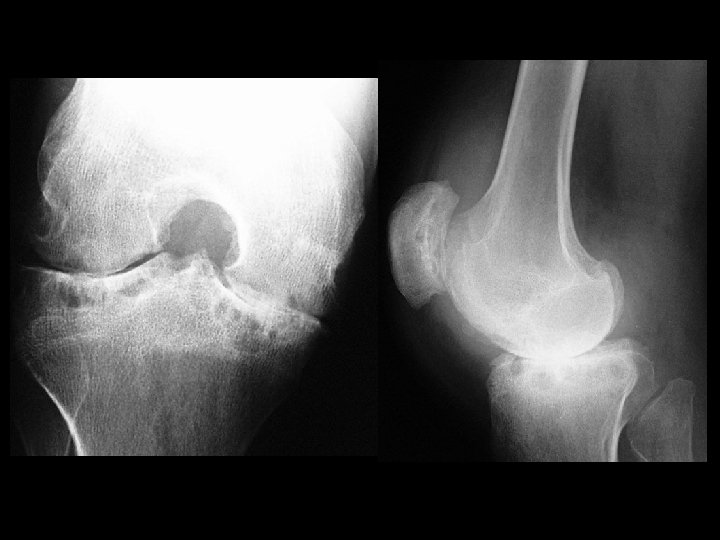

Hemophilia & secondary osteoarthritis • Findings: – severe secondary OA – flared metaphyses – widening of intercondylar tunnel – dense joint effusion • ddx: – JRA